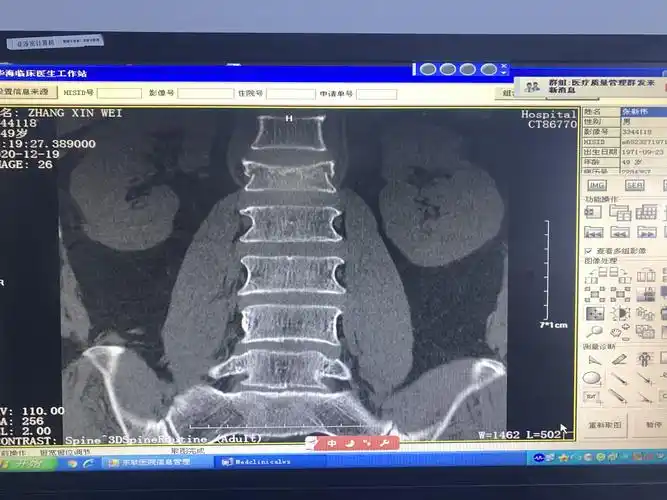

38床, 腰1椎体压缩性骨折

75岁腰椎压缩性骨折患者椎体成型手术一例

问题:第11和12腰椎压缩性骨折